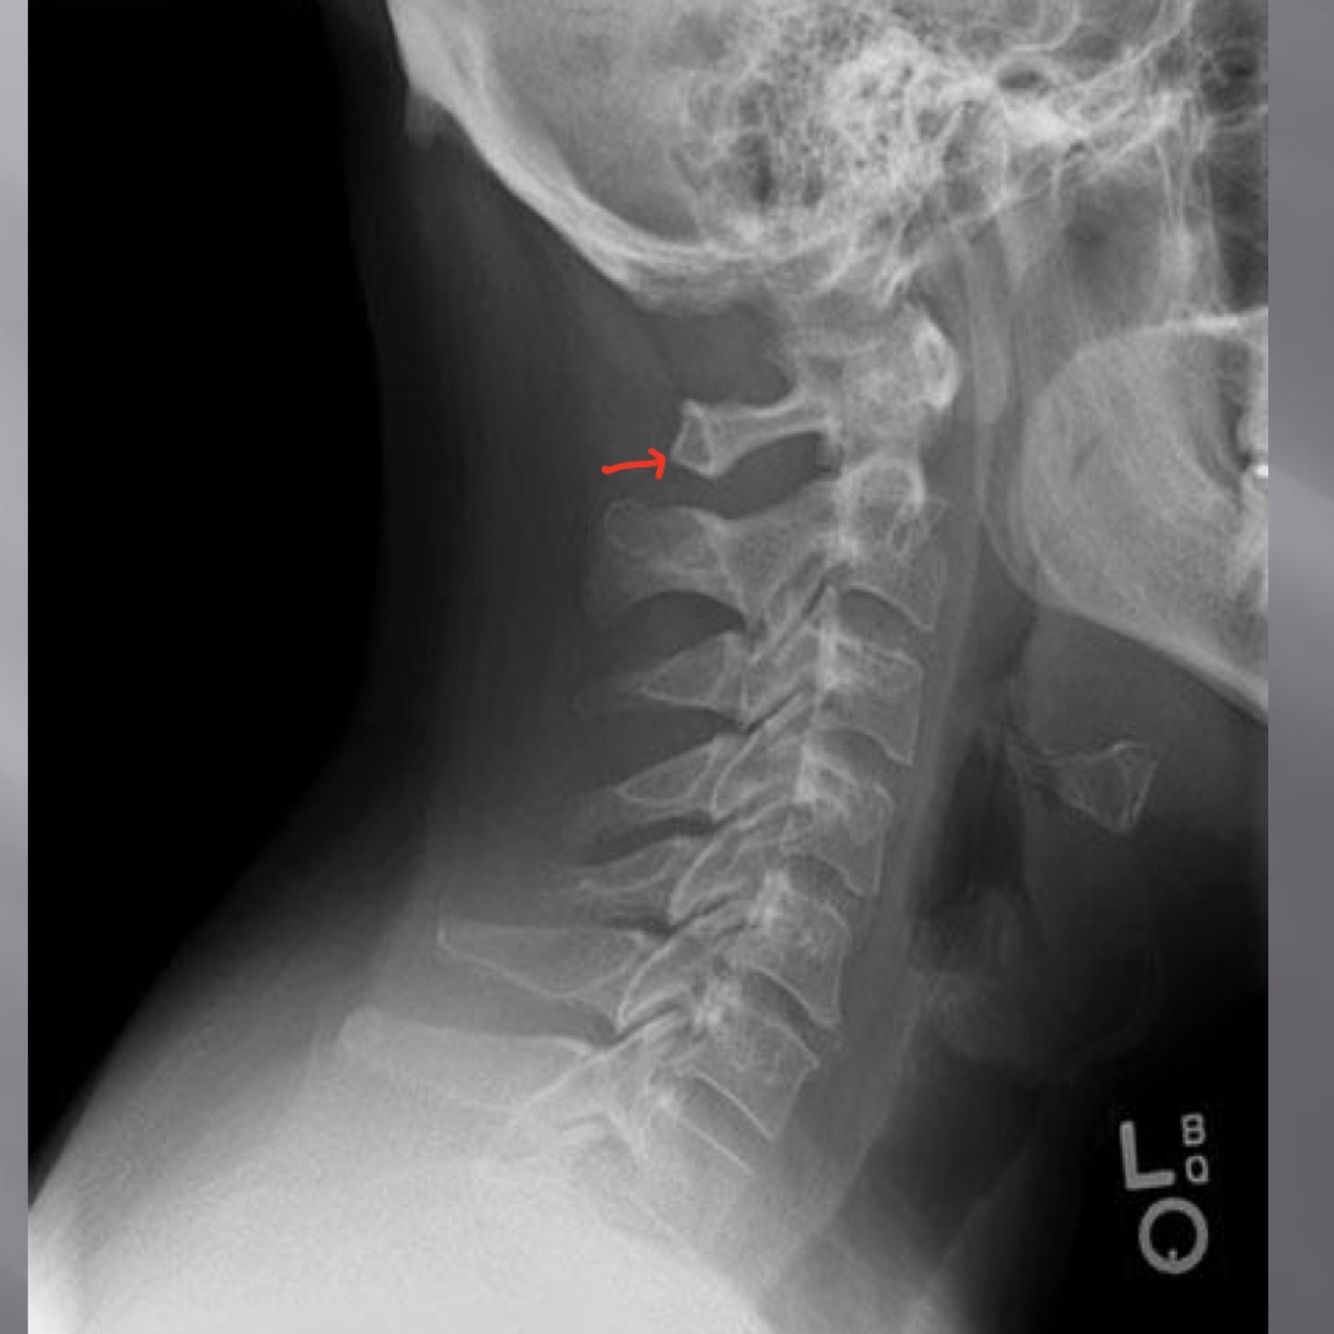

LATERAL CERVICAL LANDMARKS lateral cervical view

dens

posterior arch of C1

vertebral body c2-c7

anterior tubercle c1

zygapophyseal joints

superior endplate tips

inferior endplate tips

Lateral cervical view

disc spaces

atlanto-dental interspace